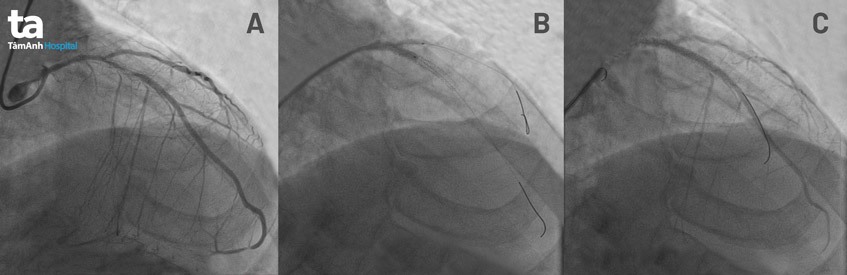

BS.CKII Huỳnh Ngọc Long, Giám đốc Trung tâm can thiệp mạch chia sẻ: “Kết quả chụp DSA mạch vành cho thấy, bệnh nhân bị tắc hoàn toàn hai mạch máu nuôi tim (mạch vành phải và động mạch mũ), nhánh còn lại (liên thất trước) hẹp hơn 90%. Chính vì thế, mục tiêu của chúng tôi khi thông tim là nong nhánh mạch máu sắp tắc, và quá trình nong phải thật cẩn trọng. Bởi lẽ, bệnh nhân chỉ còn lại một nhánh “độc đạo” này để đưa máu nuôi tim. Nếu xử lý không tốt trong quá trình đưa bóng vào, bệnh nhân có thể bị rung thất và tử vong ngay lập tức”.

Ngoài ra, hình ảnh mạch máu được dựng hình qua hệ thống chụp mạch vành DSA cũng cho thấy đoạn mạch liên thất trước bị hẹp còn đi ngang một “ngã ba” – giao với một mạch máu khác (nhánh xiên), chèn ép nhánh này. Do vậy, bác sĩ Long và ekip quyết định tiến hành thủ thuật Kissing Balloon – nong 2 bóng cùng lúc để mở rộng cả 2 nhánh.

Xác định đây là thủ thuật phức tạp, nguy cơ rủi ro cao cho người bệnh, bác sĩ Long và ekip cẩn trọng trong từng thao tác. Đầu tiên, một quả bóng cứng được đưa vào lòng mạch với áp lực cao (16 atm) để ép mô tăng sinh và stent cũ ra ngoài. Quá trình đưa bóng vào và làm xẹp bóng này (gọi là quá trình bơm bóng nhanh – xả bóng nhanh tránh rung thất) được tiến hành liên tục nhiều lần, mỗi lần trong tích tắc (từ 1-2 giây) để tránh nguy cơ rung thất. Sau khi nong được nhánh liên thất trước và lòng mạch máu được nong từ từ cho đến khi đủ rộng để đưa được ống stent vào. Hơn nữa, vì đây là lần tái thông lòng mạch nên stent mới phải đảm bảo áp sát stent cũ, không có kẽ hở để giảm tỷ lệ huyết khối cũng như nguy cơ tái hẹp về sau. Nhánh mạch máu xiên cũng được nong thành công, mở rộng như mục tiêu đặt ra ban đầu.